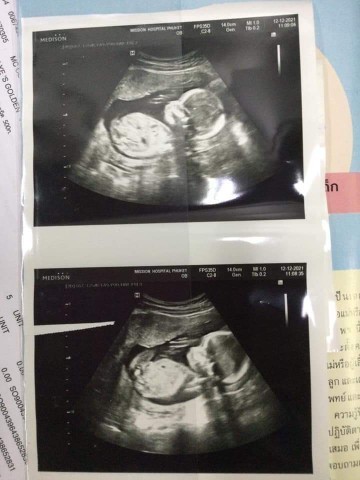

อัลตร้าซาวด์

อายุครรภ์ในใบอุลตราซาวด์ ตรงกับ ปจด รอบสุดท้ายไหมคะ